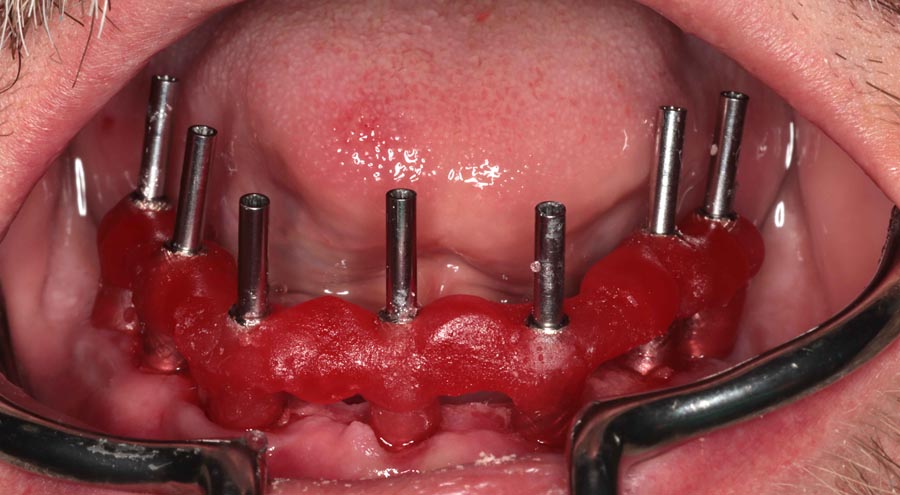

All upper teeth extracted, implants and bone filler placed. Not, we did not remove any bone and attempted to disturb the gums minimally.

Immediate temporary, implant bridge delivered. This is one day post-surgery and delivery of temporary.